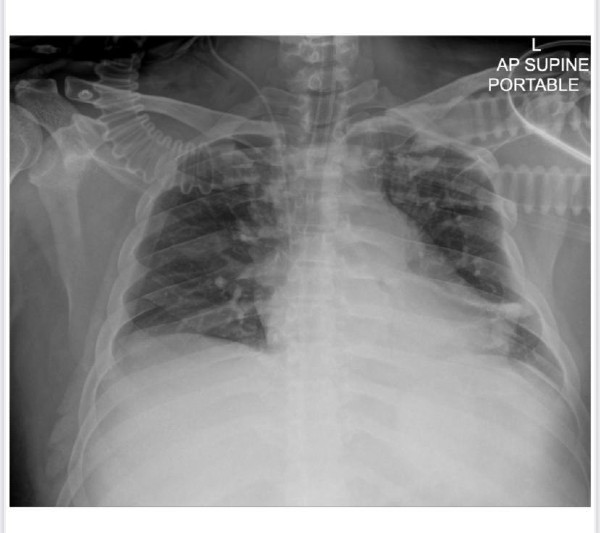

- Ориентировочно 25 числа он уже был там и 31 января поступил в клинику с жалобой на рвоту, - делится Тихон. - Впоследствии его прокапали и ситуация нормализовалась, но 2 февраля госпитализировали, и по сей день он находится в состоянии искусственной комы и на гемодиализе. По диагнозам у него сейчас выявлена пневмония, легочная недостаточность, сепсис, острый панкреатит. Они (представители больницы - «НГ») с меня потребовали 500 000 бат, что эквивалентно 8 млн тенге. Страховая покрыла расходы на лечение в размере $10 000, это страховка, которую приобрели по путевке. Далее родные должны выплачивать суммы лечения самостоятельно. Я запускаю сбор денег на его лечение на данный момент, чтобы была возможность вылечить его и вернуть назад в Казахстан. В свою очередь от волонтеров я ожидаю помощь с организацией сбора денег на оплату лечения моего брата в Таиланде.

Фото предоставлены Тихоном ВИВТОНЕНКО